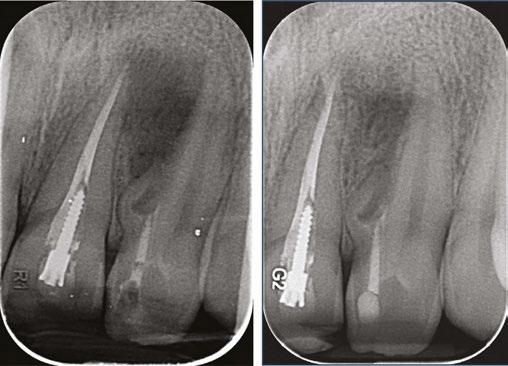

Figure 1: CBCT scan of the tooth demonstrating the radiolucent lesion surrounding the DI and extending to the apex of the central incisor Figures 2A-2D: 2A. Periapical radiograph of the dens. 2B. Hedstrom file in the invagination. 2C. The obturated enamel lining of the invagination with BC putty. 2D. Healing of the periapical lesion in the 1-year follow-up

A periapical radiograph demonstrated a DI with an apical radiolucency extending from the mesial aspect of the lateral incisor towards the apex and distal aspect of the central incisor. A slight inclination of the root of the maxillary left lateral incisor was observed in the periapical radiograph.

Considering the irregular anatomy of the tooth, the patient was referred for a CBCT scan.

The CBCT scan confirmed the presence of a Type IIIa invagination and a large radiolucent lesion that was associated with the invagination in the lateral incisor and extended mesially towards the apex of the central incisor. Since the apex of the main canal in the lateral incisor was not involved, it was decided to limit the treatment to the invagination. The diagnosis of the periapex of the previously treated central incisor was unclear; there was either periapical healing or asymptomatic apical periodontitis; therefore, no intervention was done, and the tooth was kept for follow-up.

During the first appointment, a palatal access cavity was prepared under a surgical operating microscope based on the external morphology of the tooth and the CBCT scan. After gaining access to the invagination, the enamel-lined canal was conservatively enlarged using an ultrasonic tip. Biomechanical preparation was based on copious irrigation with 2.5% Sodium hypochlorite (NaOCl) and 17% ethylene diamine tetra-acetic acid (EDTA) and the use of the XP Finisher (FKG Dentaire Sarl, La Chaux-de-Fonds, Switzerland). A calcium hydroxide dressing was placed using a spiral Lentulo, and the access cavity was temporized with Coltosol® (Coltene Whaledent) provisional filling material.

At the second appointment (2 weeks later), the patient was asymptomatic. The invagination was irrigated with 2.5% NaOCl and 17% EDTA, and the enamel-lined invagination was obturated with BC Putty (EndoSequence®, BC RRM™ Fast Set, Brasseler). The access cavity was then filled with a Coltosol F® (Coltene Whaledent) and Fuji Equia glass ionomer (GC America) as a temporary filling to seal the access. One week later, it was replaced by a permanent composite restoration.

One year later, the tooth was asymptomatic, with no tenderness to palpation or percussion, and normal mobility was observed. Radiographic examination demonstrated healing of the lesion. Complete healing was observed around the apex of the central incisor, which was symptom-free, and therefore no intervention was necessary for this tooth.